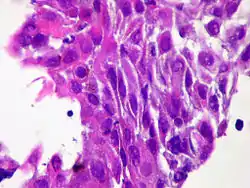

سرطانة الغدة الدرقية الحرشفية الخلية (بالإنجليزية: Squamous-cell thyroid carcinoma)[1] هو ورم خبيث نادر يصيب الغدة الدرقية، يتكون من خلايا ورمية ذات تمايز حرشفي مميز. يمثل هذا النوع من السرطان أقل من 1٪ من الأورام الخبيثة في الغدة الدرقية.[2]يعتبر سرطان الخلايا الحرشفية في الغدة الدرقية ورم نادر وعدواني وقاتل للغاية. غالباً ما يترافق مع سرطان الغدة الدرقية الحليمي و الكشمي، وحدوثه بشكل منفرد من غير وجود أورام أخرى، يعتبر نادر للغاية.